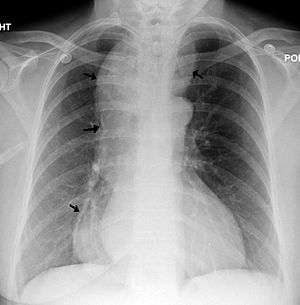

A chest X-ray showing achalasia ( arrows point to the outline of the massively dilated esophagus ) | |